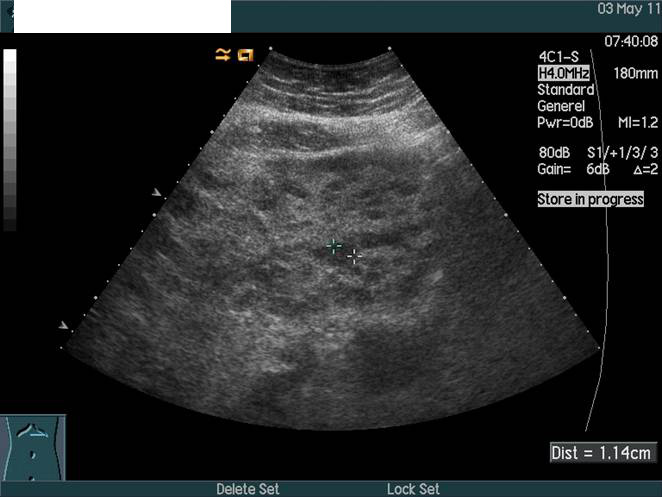

Lever, Metastaser, CT og Ultralyd

CT- og UL-skanning af leveren uden kontrast. CT (nedenfor) viser stor lever, men UL (ovenfor) viser variende ekkoer forenelig med metastaser. CT-diagnostik af levermetastaser kræver administration af kontraststof og skanning i den rette fase af kontraststoffets passage af leveren.